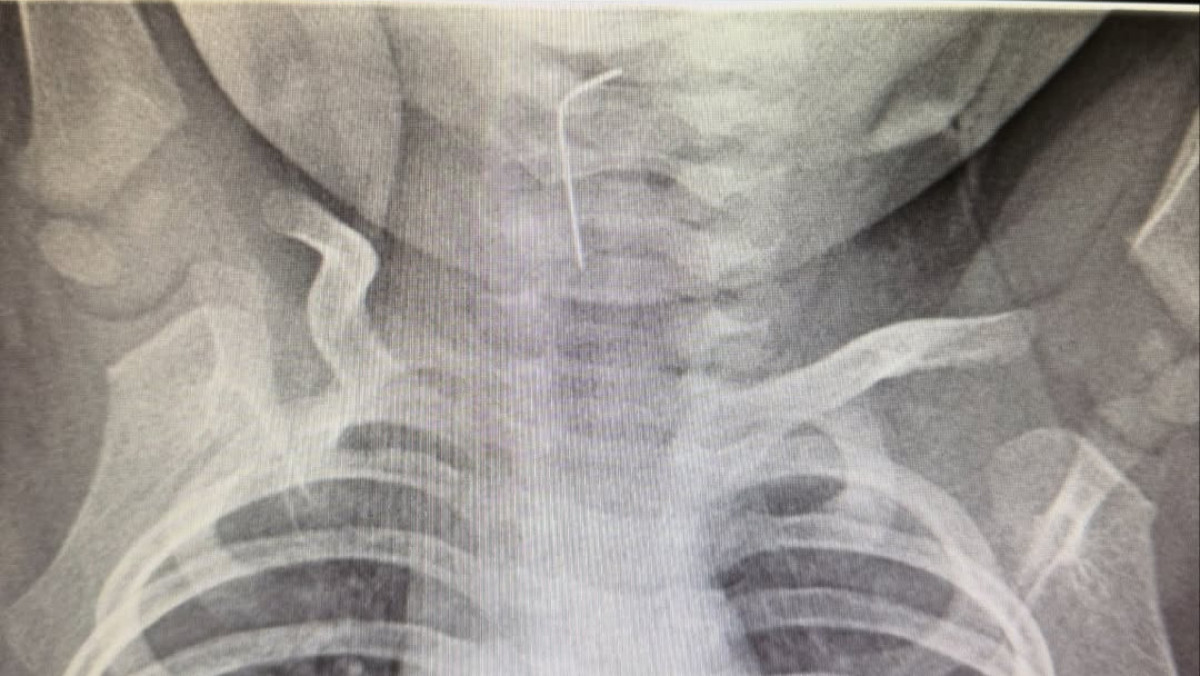

"Белгілі болғандай, сәби абайсызда ине жұтып қойған. Тез арада аурухана мамандары – хирург Темірбеков Мұхагали және эндоскопист Ырысқұлов Бабыр эндоскопиялық әдісті қолдана отырып, рентгенологиялық тексеру жүргізді. Нәтижесінде бөгде заттың нақты орналасқан орнын анықтап, өңеште тұрып қалған бөгде затты сәтті түрде алып шықты", – деп хабарлады Түркістан облысы әкімдігінің баспасөз қызметі.

Медициналық көмек жедел әрі кәсіби көрсетілуінің нәтижесінде ықтимал асқынулардың алдын алу жұмыстары сәтті аяқталды.

Дәрігерлердің айтуынша, қазіргі таңда баланың жағдайы жақсы. Сәби дәрігерлердің бақылауында болып, үйіне шығарылды.